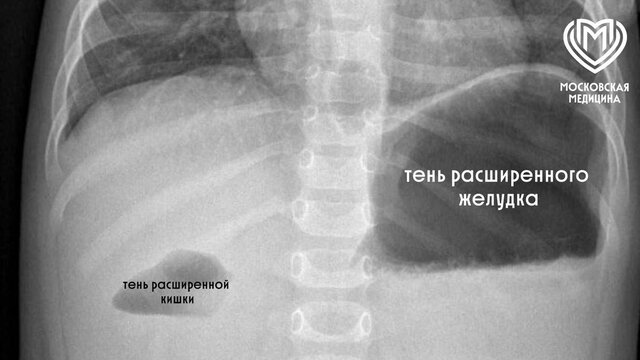

Столичные врачи спасли годовалую девочку, проглотившую силиконовый шар